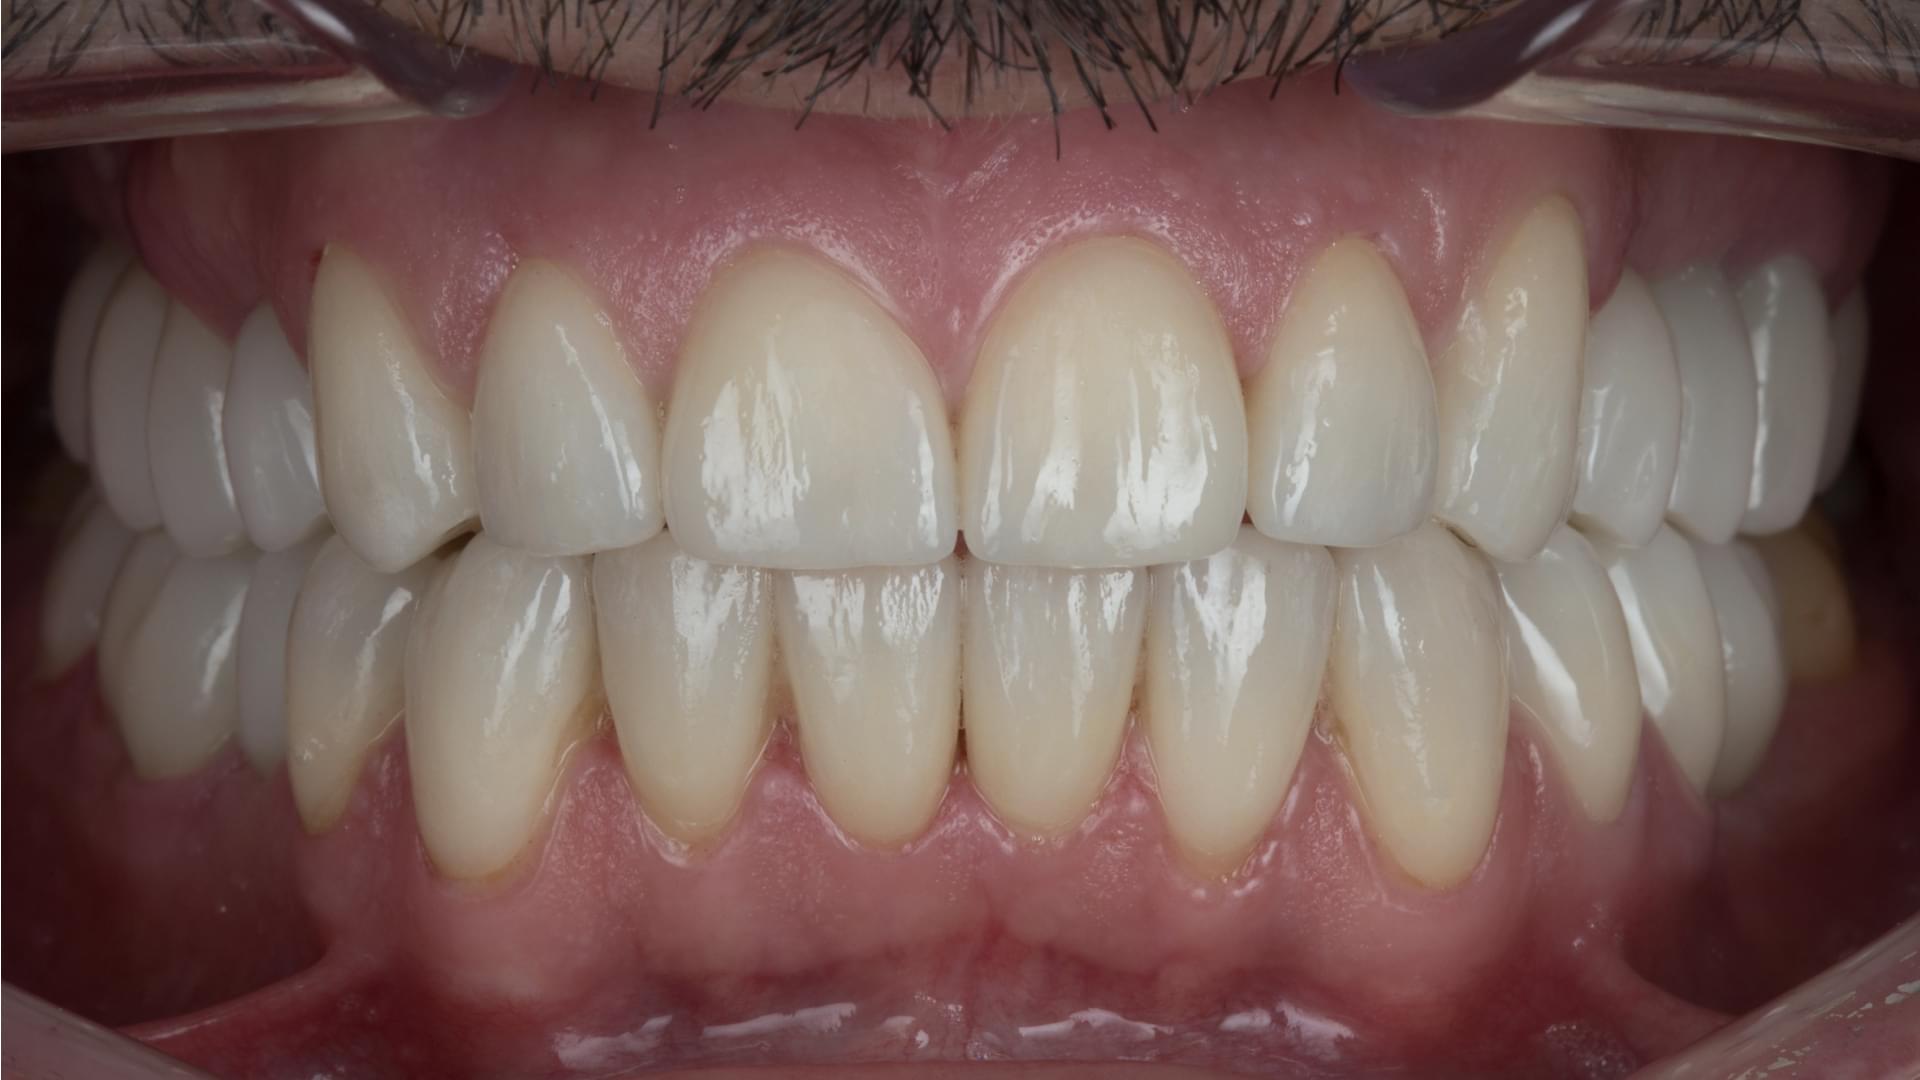

Atunci când are loc devitalizarea unui dinte, acesta trebuie extras din cauza infecției canalului radicular. Pentru restabilirea dintelui, rădăcinile infectate pot fi îndepărtate și înlocuite cu un implant dentar. Acum este posibilă înlocuirea dinților bolnavi cu implanturi și coroane din Zirconiu, și obținerea unui zâmbet natural și estetic, planificat cu ajutorul computerului.

Cea mai eficientă metodă, în cazul pierderii dinților, este înlocuirea acestora cu punți sau implanturi dentare. Pentru a avea niște gingii sănătoase este recomandată inserarea implanturilor dentare peste care, în cele din urmă, se inserează coroanele dentare din Zirconiu, astfel obținând un zâmbet natural și estetic. Toată planificarea are loc cu ajutorul computerului.

Acoperirea dinților cu punți și coroane metalo-ceramice, odată cu trecerea timpului, afectează gingiile și rădăcinile. Atunci când are loc îndepărtarea gingiilor de punțile metalo-ceramice, se descoperă un profil metalic negru și inestetic. De asemenea, are loc acumularea alimentelor și carierea rădăcinilor care susțin capsulele. Acum este posibilă înlocuirea coroanelor și punților cu implanturi dentare, astfel obținând un zâmbet natural și estetic.

Implanturi Dentare 🔥 Cazuri finisate #1